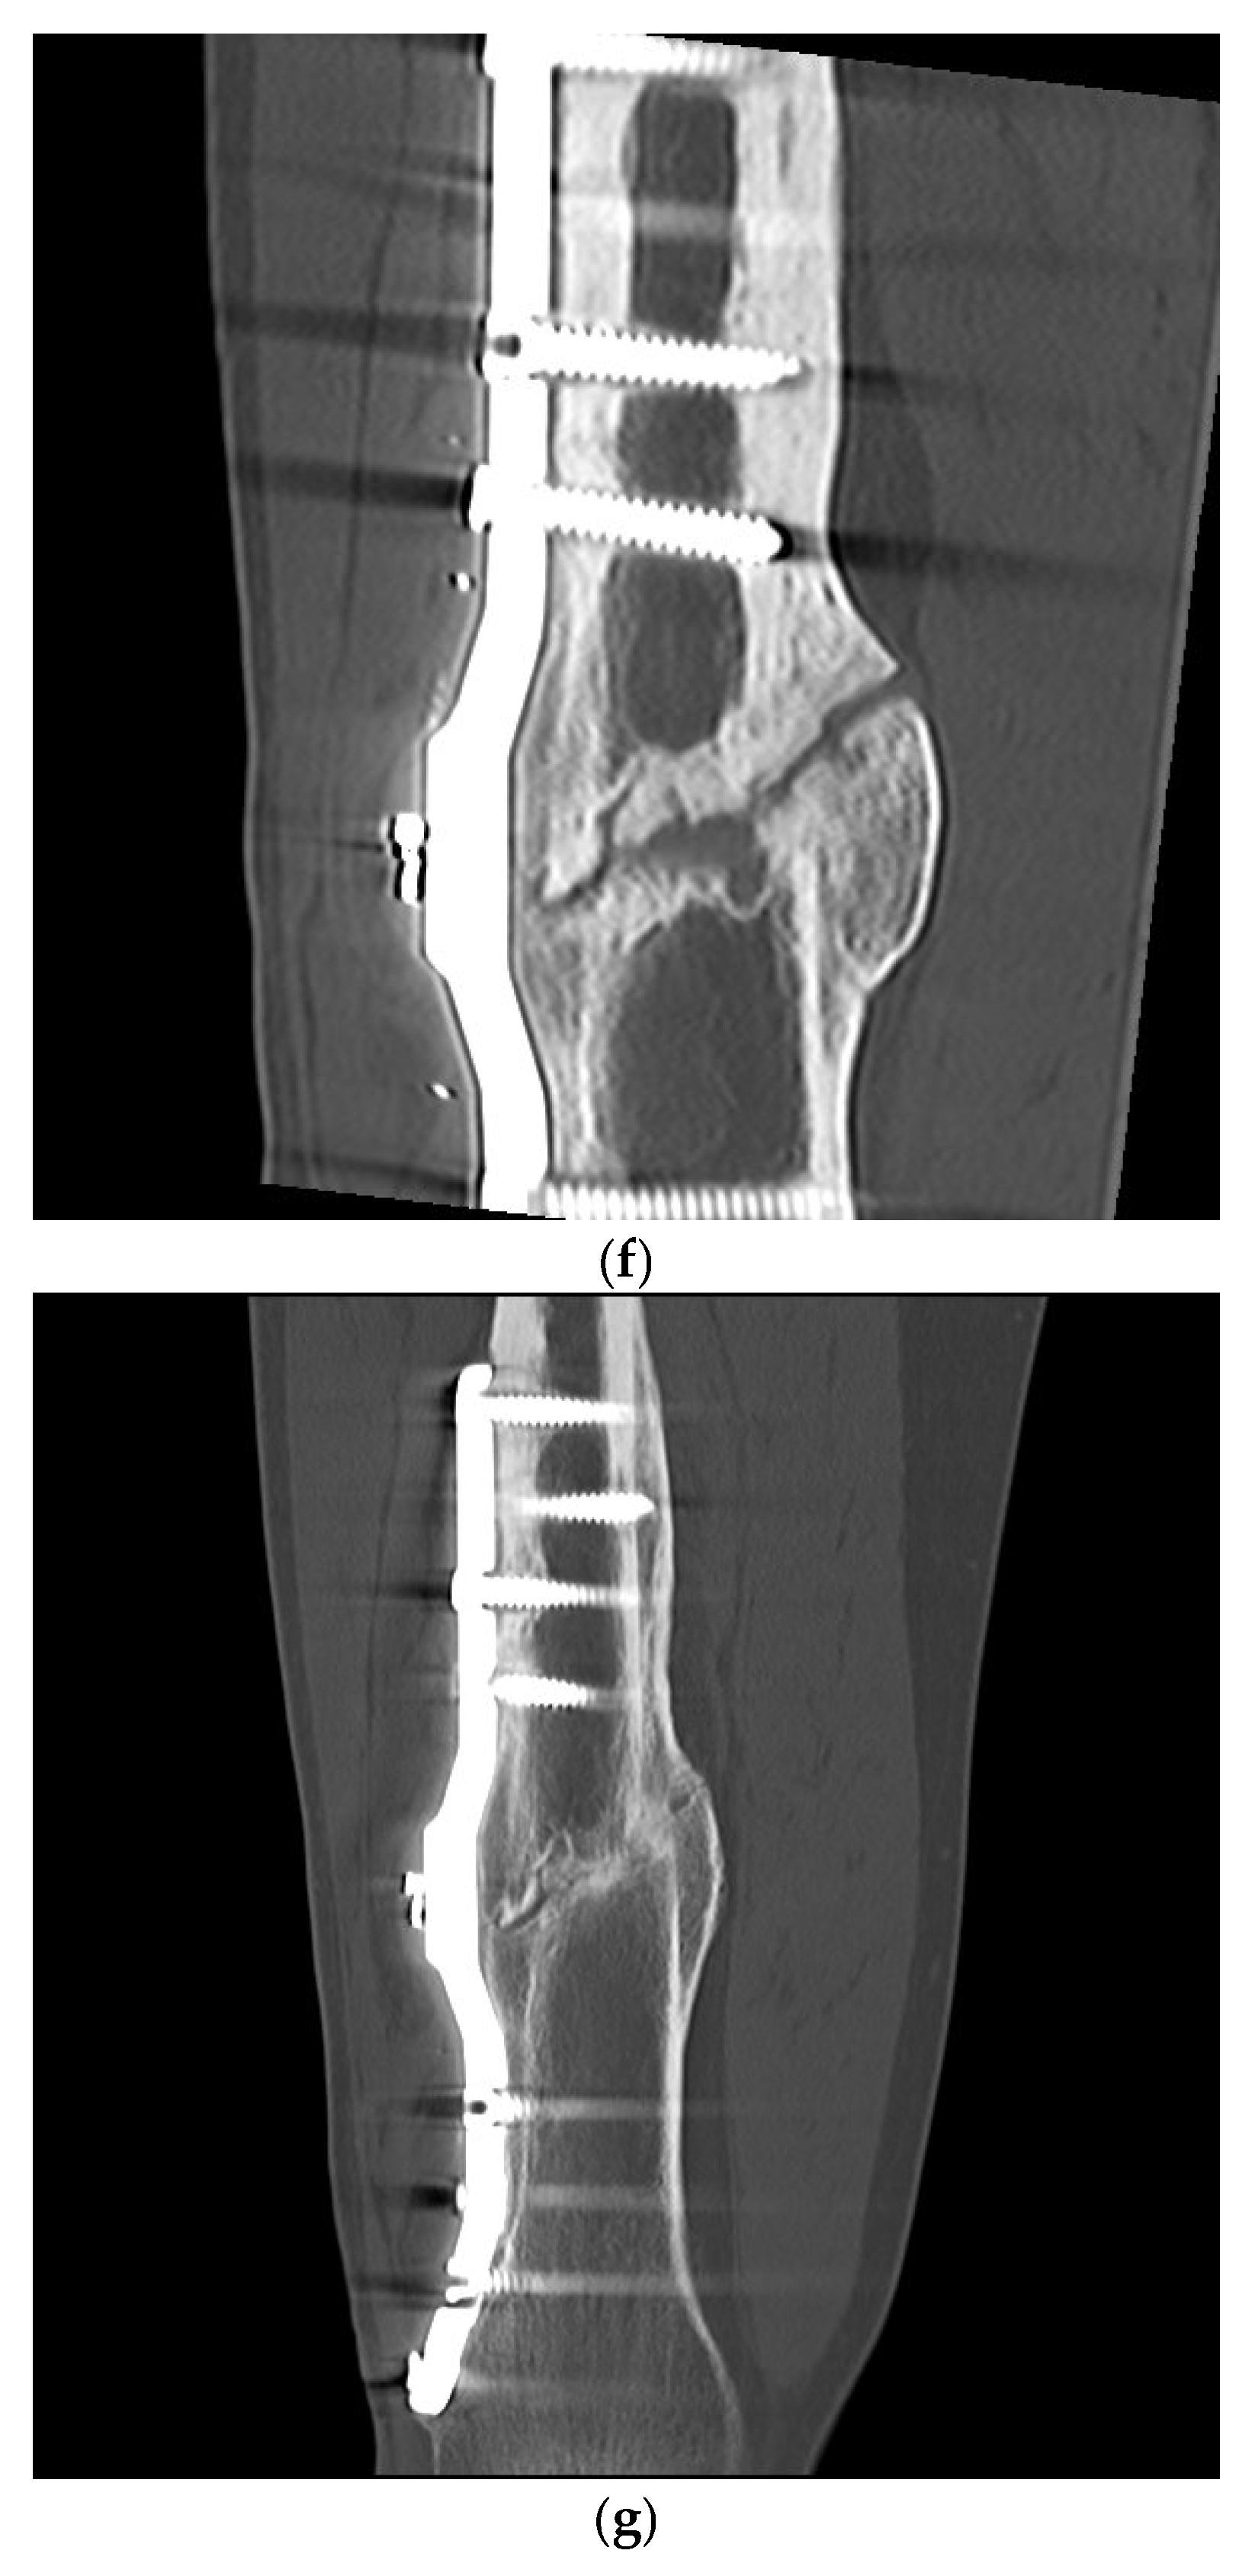

Postoperative Procedure and Further Course